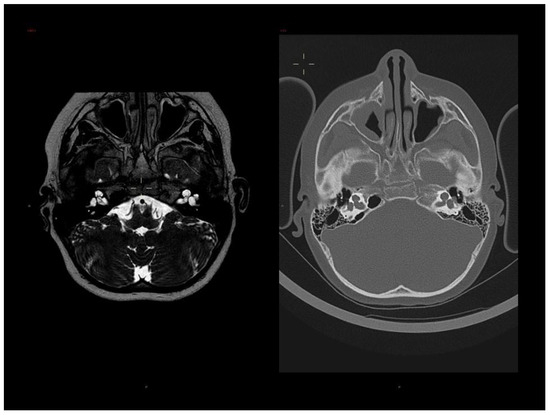

3.1. Clinical Report